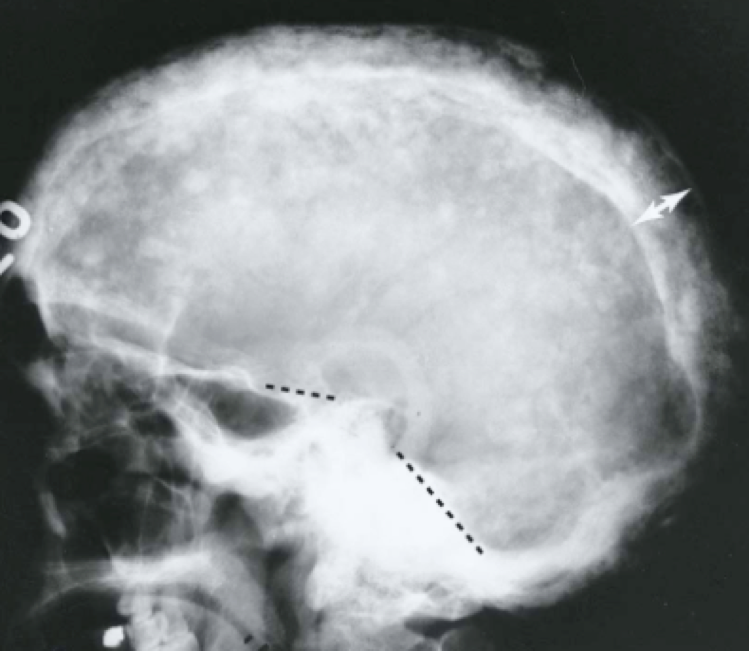

Question 6

Question

What are the three signs of basilar skull fx?

Answer

• raccoon eyes

• terrible cough

• severe sore throat

• CSF rhinorrhea

• otorrhea